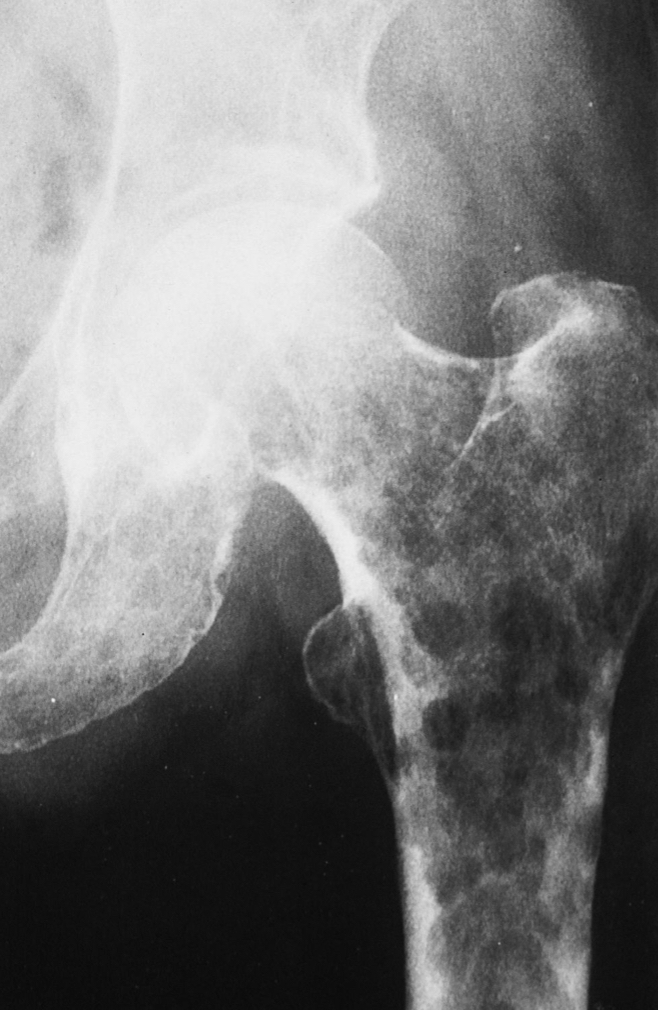

what is this?

multiple myeloma